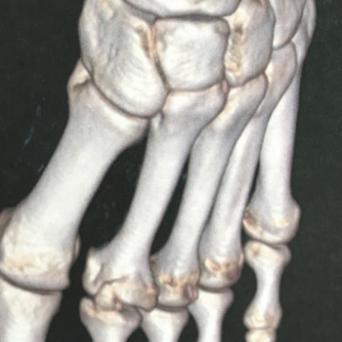

Douleur au poignet chez la femme enceinte : que faire ?🎬

Les changements hormonaux de la grossesse et du post-partum sont une cause fréquente de douleurs du poignet et de la main. Les principaux diagnostics à évoquer sont le syndrome du canal carpien et la ténosynovite de De Quervain. Souvent négligés, ces troubles altèrent la qualité de vie de la femme et peuvent évoluer vers des formes chroniques. Quelle prise en charge proposer ? Quel suivi ? Flash interview du Dr Marc-Olivier Falcone, chirurgien orthopédiste et traumatologue, Paris.